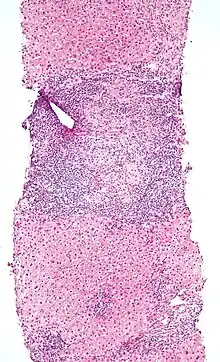

Intestinal IELs are long-lived resistant effector cells spread along the entire length of intestine, where they patrol the space between intestinal epithelial cells (IEC) and the basement membrane (the intraepithelial space). Epithelium of small intestine contains approximately 1 IEL per 10 enterocytes.[3] Due to their constant exposure to of antigens at mucosal barrier, they have unique antigen-experienced activated phenotypes and they constantly express CD103 (αE integrin), that is distinct from the conventional T cells in the intestine.[3] IELs are mainly T cells with mixture of subsets. They are divided into two groups – conventional and unconventional IELs.[4]

An elevated IEL population, as determined by biopsy, typically indicates ongoing inflammation within the mucosa. In diseases such as celiac sprue, IEL elevation throughout the small intestine is one of many specific markers.[1] IELs have heightened activated status that can lead to inflammatory disease such as IBD, promote cancer development and progression,[12] or become the malignant cells in enteropathy-associated T-cell lymphoma, a lymphoma that is a complication of celiac sprue.[13][14]